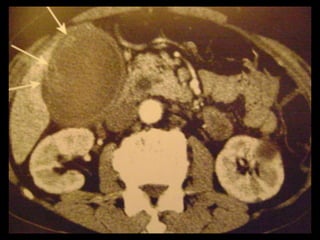

Achados na TC: cálculos biliares, espessamento da

parede, alterações inflamatórias

perivesiculares, bile com alta

atenuação, borramento da interface VB-fígado e

aumento transitório da atenuação do fígado

perivesicular;

Colecistite aguda US é a modalidade de imagem de escolha; Em geral, a TC é realizada para avaliar pacientes com suspeita de complicações do quadro de colecistite aguda, como perfuração por exemplo. Achados na TC: cálculos biliares, espessamento da parede, alterações inflamatórias perivesiculares, bile com alta atenuação, borramento da interface VB-fígado e aumento transitório da atenuação do fígado perivesicular;